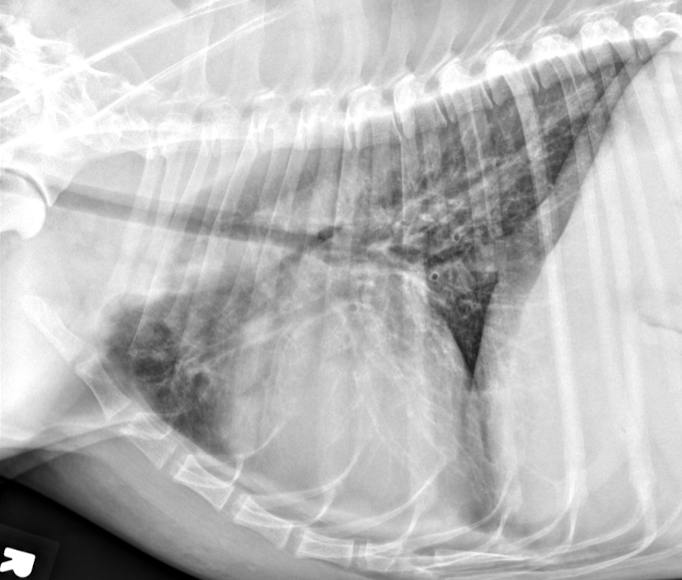

Lung Pattern?

Atelectasis *Red = alveolar pattern*